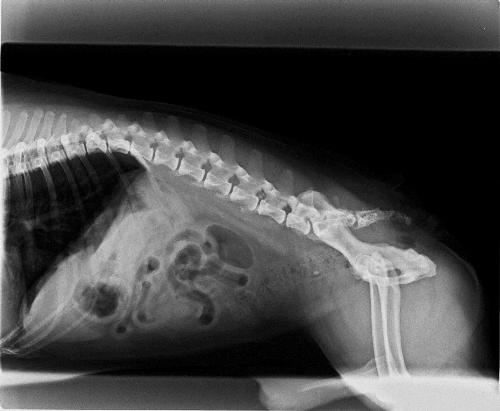

Il cancro canino può essere il peggior incubo dei proprietari di cani e pochi altri tumori sono terrificanti quanto il cancro alle ossa L'osteosarcoma è la forma più comune di tumore osseo nei cani, che rappresenta circa l'85% dei tumori ossei totali È aggressivo, veloce da diffondere o metastatizzare e difficile da trattare. Tumore ai polmoni sopravvivenza Il tumore al polmone ha vari stadi, in base ai quali si decide la terapia adeguata Quando ci si trova davanti al primo e al secondo stadio, un intervento. Berkeley Electronic Press Selected Works.

Fatti p > cancro alla spina dorsale canina è più frequente tra i cani più di sei anni La maggior parte dei tumori spinali sono in gran parte a causa della maggiore pressione sulla colonna vertebrale a causa di un tumore adiacenti all'interno dell'osso. Come diagnosticarlo Il lipoma alla schiena è un tumore generalmente asintomatico, pertanto per scoprire se si è affetti da questa neoplasia benigna è necessario sottoporsi ad alcune indagini cliniche con l'impiego di strumentazioni Un'ecocardiografia mostra evidenti i contorni del lipoma sul referto compare la massa alla schiena, anche se i contorni non saranno ben nitidi. Considerati da un punto di vista “tecnico”, essi rappresentano il 15% dei tumori del sistema nervoso centrale A seconda dello sviluppo si distinguono in intramidollare (5%) – nel midollo, intradurale extramidollare (fuori dal midollo ma all’interno delle meningi), con possibile estensione extradurale (40%), ed extradurale (55%) (all’ interno del canale vertebrale, ma fuori dal.

Mi e'stato diagnosticato un tumore alla spina dorsale vorrrei sapere se ci sono cure adeguate e quali sono Risposta del 24 ottobre 05 Risposta a cura di Dott MATTEO LIBROIA Sarebbe utile una visita specialistica neurochirugica, anche perchè non è specificato il tipo di neoplasia descritta. Fatti p > cancro alla spina dorsale canina è più frequente tra i cani più di sei anni La maggior parte dei tumori spinali sono in gran parte a causa della maggiore pressione sulla colonna vertebrale a causa di un tumore adiacenti all'interno dell'osso. Il tumore alla spina dorsale comprende un tumore alle ossa Tumori al fegato,polmoni e ossa sono tra i peggiori esistenti in natura Stagli vicino e dagli tanto tanto conforto!!!.